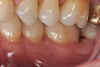

Fig 3. Distal probing depth of 10 mm at tooth No. 19.

Figure 3

In the case presented, a 56-year-old healthy nonsmoking male patient, diagnosed with periodontitis stage III, localized, grade B, had been under care in a private practice periodontal office (RAL) for 25 years. He had a history of good compliance with his treatment (full-mouth plaque score <20%). During the COVID-19 pandemic, the patient missed three supportive periodontal therapy (SPT) visits over a year, resulting in periodontal breakdown interproximal between teeth Nos. 18 and 19 (mandibular left second and first molars, respectively). At his most recent periodontal maintenance visit, significantly increased periodontal probing depths of up to 10 mm with bleeding on probing were noted (Figure 1 through Figure 3). The periapical radiograph revealed a deep, narrow three-wall intrabony defect at the distal aspect of tooth No. 19, with class I buccal furcation involvement (Figure 4). According to the periodontal risk score (PRS),15 formerly known as the Miller-McEntire periodontal prognosis index, the tooth prognosis at the patient's initial examination was "good" (score = 5), taking into account that he was unaware of his hemoglobin A1C (HbA1c) levels. This scoring motivated the patient to be tested, and his follow-up HbA1c was <6%, thus reducing his PRS to 3, which was considered "excellent," as the PRS target goal for regenerative procedures is a score of <5.15